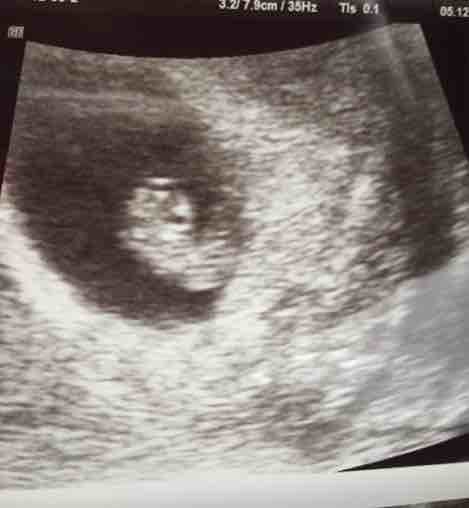

A 7 week scan is sometimes called a dating scan , because it's an accurate way of assessing a baby's age and growth . If you've had any complications such as blood loss, an ultrasound could help identify the cause and source of the bleeding .

The common first step will be a dating scan between 7-10 weeks as we like to check your baby before 10 weeks . Why scan at 7 weeks ? An ultrasound is performed at this stage of pregnancy to confirm your due date, confirm if you are having singles, twins or more and to visualise your baby's heart beating . Before 7 weeks it may be too early to acquire this information . How is the scan performed?

How accurate are dating scans ? A dating scan is the most accurate way to predict your due date, also known as your estimated date of delivery (EDD) . The point of the scan is to work out how many weeks pregnant you are . You may have calculated the length of your pregnancy from the first day of your last menstrual period (LMP) . However, conception doesn't actually occur until around 14 days after your LMP, or later if your cycle is longer than 28 days .